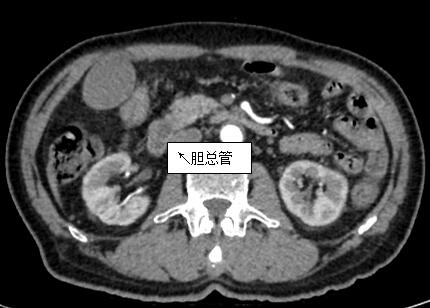

69歲王姓患者,因“發(fā)現(xiàn)無痛性黃疸1月”入院,根據(jù)患者病史,患者診斷傾向于壺腹部腫瘤所致梗阻性黃疸。予以完善腹部CT及上腹部MRI加MRCP均顯示肝內(nèi)外膽管擴(kuò)張,未發(fā)現(xiàn)明顯膽管,胰腺及十二指腸乳頭部腫瘤,且患者CA199正常。以前醫(yī)院未引進(jìn)超聲內(nèi)鏡,這類患者到此就遇到診斷瓶頸。此患者經(jīng)過消化內(nèi)科張丹霞副主任醫(yī)師完善超聲內(nèi)鏡檢查后,可以清楚顯示膽總管下段壁內(nèi)軟組織占位?;颊咄ㄟ^超聲內(nèi)鏡檢查診斷明確,轉(zhuǎn)至肝膽外科行手術(shù)治療。

上腹部CT圖片

膽總管小腫瘤性病變CT及MRI檢查陽性率偏低,因其低代謝特征,PET-CT陽性率也偏低,超聲內(nèi)鏡對(duì)這類疾病的診斷陽性率是所有檢查中最高的,且可行穿刺活檢進(jìn)一步確診病灶性質(zhì)。